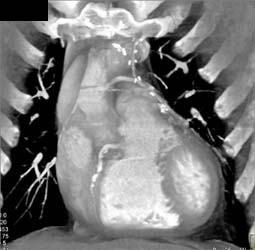

Pulmonary Embolism